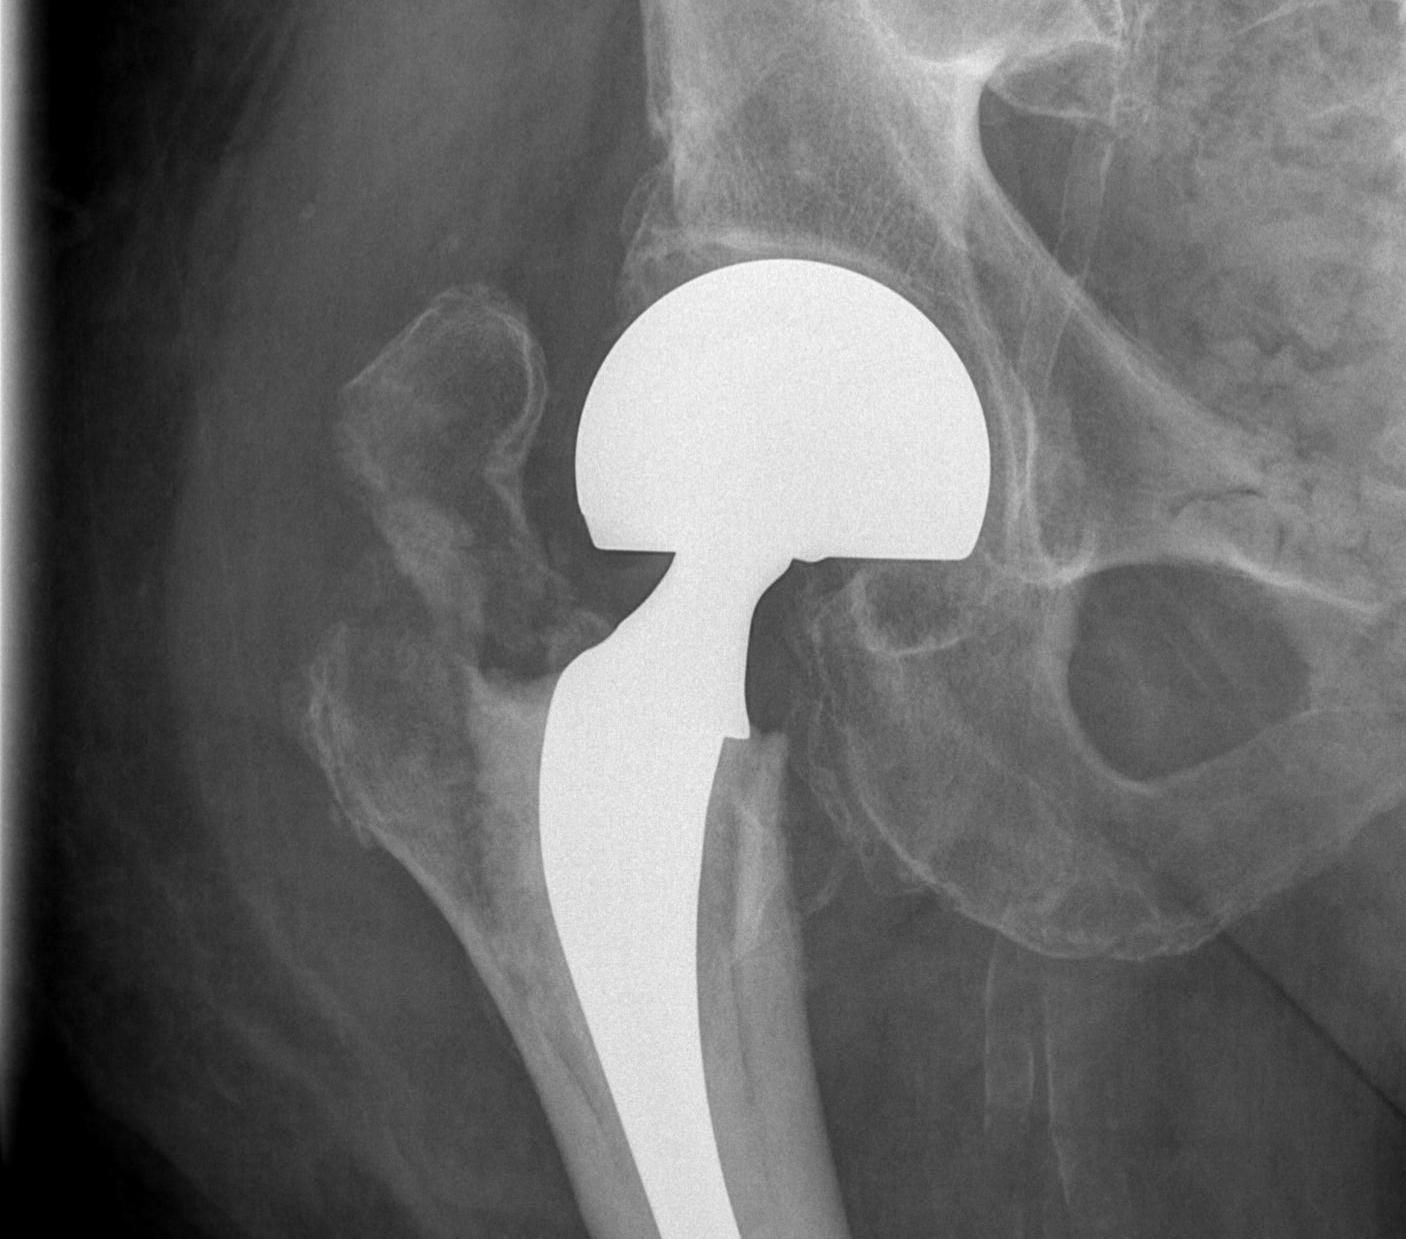

Bipolar modular

Concept

- second articulation between inner smaller head and polyethylene liner

- reduce wears on acetabulum

- improved function and less pain

- may reduce dislocation

- may have better ROM